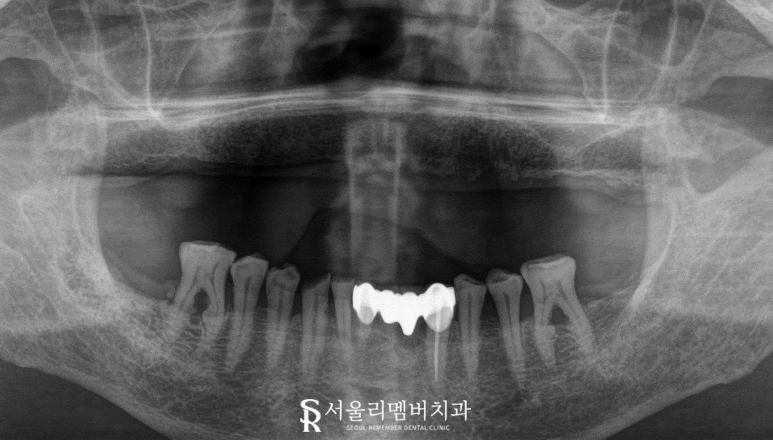

2024.02.27

이 케이스는 이가 하나도 없던 상악 전체를

임플란트로 수복하는 치료를 진행했습니다.

계획 수립을 위해

정밀한 CT 촬영과 구강 내 검사를 시행하였고,

골밀도와 사용 가능한 골량을 평가했습니다.

서울대입구역 치과 에서 보기에

이 케이스의 경우,

비용 효율성을 고려하여

7개의 픽스처를

전략적으로 배치하는 방법을

선택할 수 있겠습니다.

일반적으로 전악 식립에는

6-8개를 심는 것이 권장되는데,

상악은 하악보다 골밀도가 낮고

저작 시 더 많은 압력을

분산시켜야 되며

남아있는 잇몸뼈 중에서

단단한 초기고정력을 얻을 수 있는 부위를 고려하여

세워진 계획이라 할 수 있습니다.